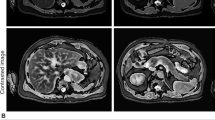

Specific US abnormalities identified in the Jena University CF cohort. (A) Pancreatic cystosis in an asymptomatic 41-year-old female patient heterozygous for G551D showing a hyperechoic pancreas (Pa) containing multiple cysts (Cy) with sizes approximately of 21 × 34 × 20 mm and 21 × 40 × 24 mm. CFAbd-Score: 82 (*range: highest burden of symptoms [0 points] to no symptoms [100 points], respectively). (B) Hyperechoic pancreas (Pa) with fat replacement as typical for pancreatic lipomatosis in a 10-year-old female patient homozygous for F508del with pancreatic insufficiency (symptom score: 95). (C) Longitudinal US image of the bowel wall in the terminal ileum measuring approximately 5 mm in a context of thickened bowel wall in a 19-year-old patient homozygous for F508del (symptom score: 81). (D) Transversal section of the small bowel showing the classic target sign appearance of intussusception in a 3-year-old female asymptomatic patient homozygous for F508del (symptom score: 96). (E) Free fluid (FF) in the right lower quadrant in a 32-year-old male patient homozygous for F508del with severe liver disease (symptom score: 80). (F) Single gallstone in a 12-year-old male asymptomatic patient heterozygous for G551D (symptom score: 100). (G) Gallbladder (arrow) in a 11-year-old female patient heterozygous for G551D measuring 18 × 4 mm in a context of micro-gallbladder (symptom score: 88). (H) US image of liver steatosis in a 4-year-old male patient homozygous for F508del, showing diffused increased echogenicity of the right lobe of the liver (Li) relative to right kidney cortex (Ki) (symptom score: 85). I) Severe periportal fibrosis (arrow) in a 28-year-old male patient heterozygous for F508del/R347P with cystic fibrosis liver disease (CFLD) (symptom score: 87). (J) Isoechoic pancreas (Pa) relative to liver in a 18 year-old female patient heterozygous for G551D with pancreatic sufficiency (PS) in longitudinal sonogram at level of the pancreatic head (symptom score: 99). (K) US scan of the appendix (Ap) in a 10-year-old asymptomatic female patient homozygous for F508del. Note the thickened aspect of the appendix (diameter of 9 mm) (symptom score: 95). (L) Enlarged mesenteric lymph nodes (LN) greater than 18 mm in the larger axis in a 10-year-old asymptomatic patient homozygous for F508del, in a context of an inflammatory etiology (symptom score: 95).